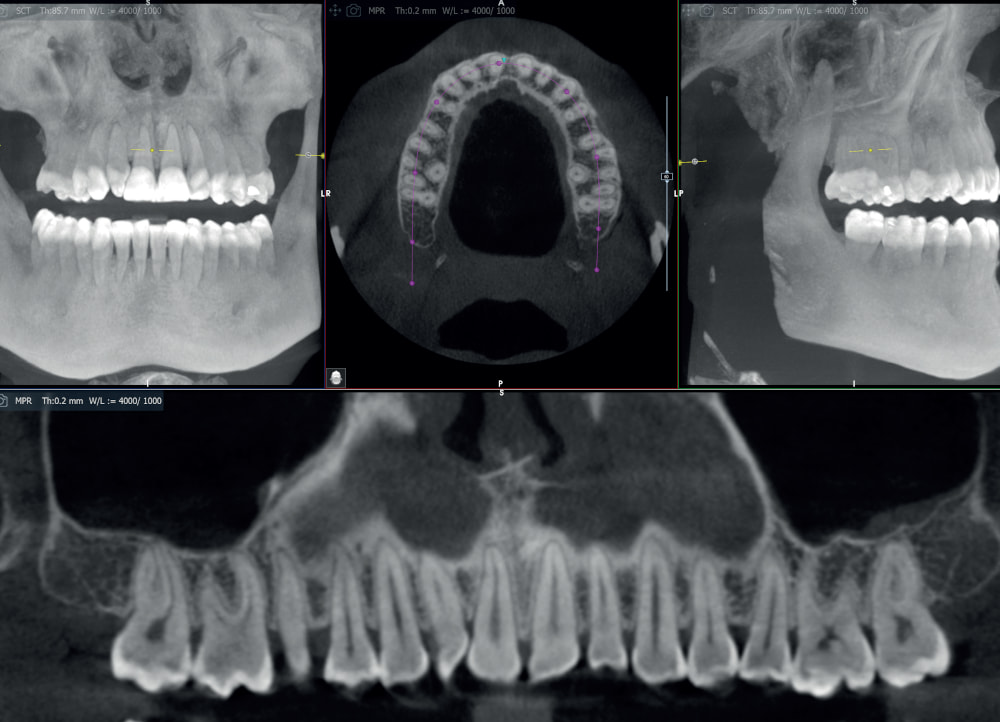

Kluczowym elementem X-MIND® optima jest detektor obsługujący rozdzielność 70 μm (w polu endodontycznym), który w połączeniu z rozszerzonym zakresem napięcia na lampie (do 90 kV) oraz najnowszą technologią IGZO Flat Panel*, zapewnia niezwykłą klarowność obrazu i doskonałe odwzorowanie anatomii pacjenta.

Dzięki szerokiemu zakresowi pól obrazowania (FOV) od 5×5 cm do 17×12 cm (Ø x H), urządzenie znajduje zastosowanie w różnorodnych zabiegach stomatologicznych – sprawdzi się zarówno w stomatologii ogólnej, jak i w specjalistycznych dziedzinach, takich jak implantologia, endodoncja, ortodoncja czy chirurgia szczękowo-twarzowa.

Wykrywanie łuku zębowego

Śledzenie przebiegu nerwu

Segmentacja zębów

Segmentacja kości

Pozycjonowanie implantu